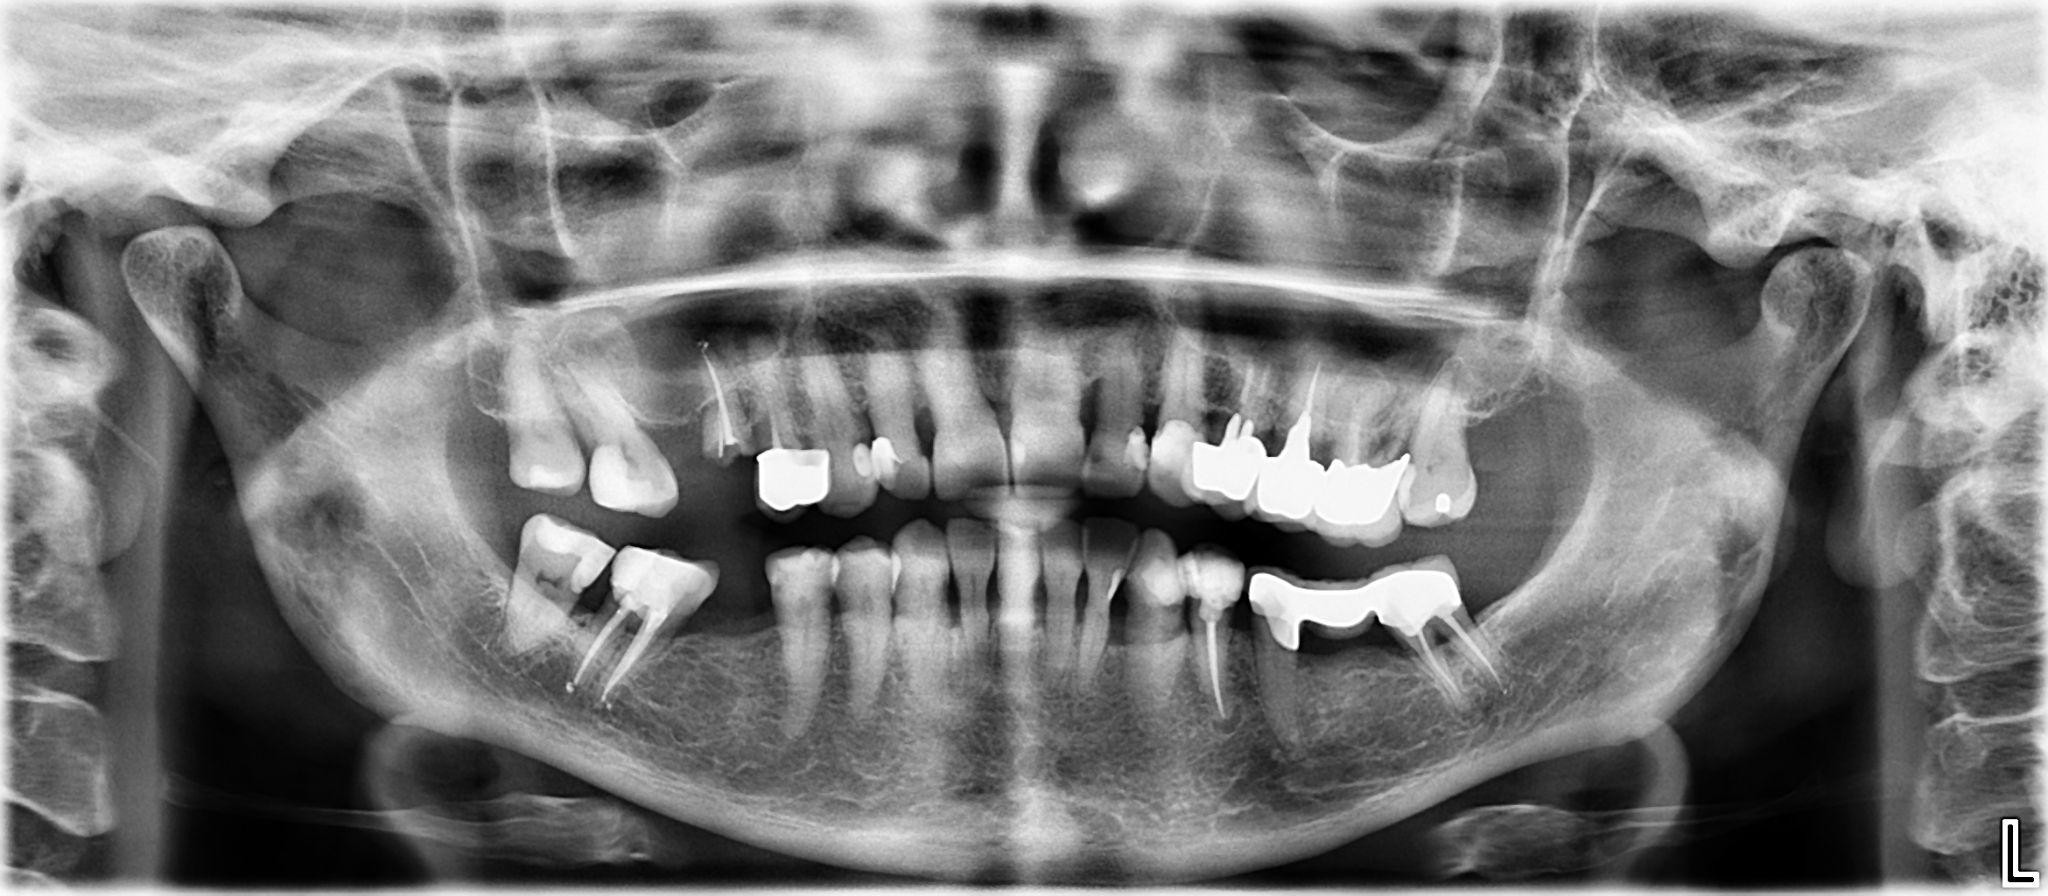

18. What option cannot be selected for the upper jaw of this panoramic X ray?

19. What option cannot be selected for the lower jaw of this panoramic X ray?

20. What option can be selected for the upper jaw of this panoramic X ray?

21. What option cannot be selected for the lower jaw of this panoramic X ray?

22. What option cannot be selected for the upper jaw of this panoramic X ray?

23. What option cannot be selected for the lower jaw of this panoramic X ray?

24. What option cannot be selected for the upper jaw of this panoramic X ray?

25. What option cannot be selected for the lower jaw of this panoramic X ray?